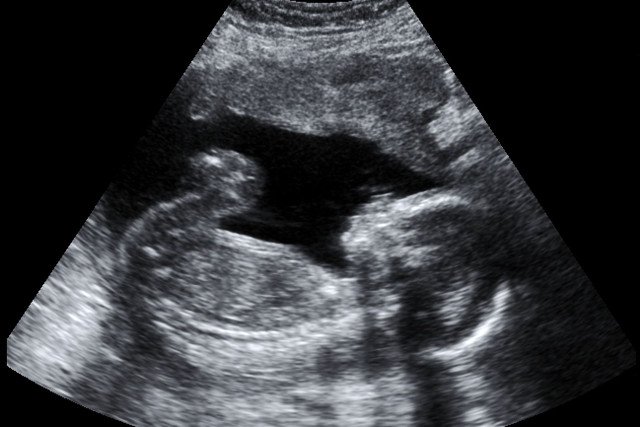

Jeszcze jest za wcześnie na kolejne obowiązkowe USG, jednak wykonane w tym czasie może już zdradzić płeć maluszka. W 14 tygodniu ciąży widoczne są już cechy płciowe.